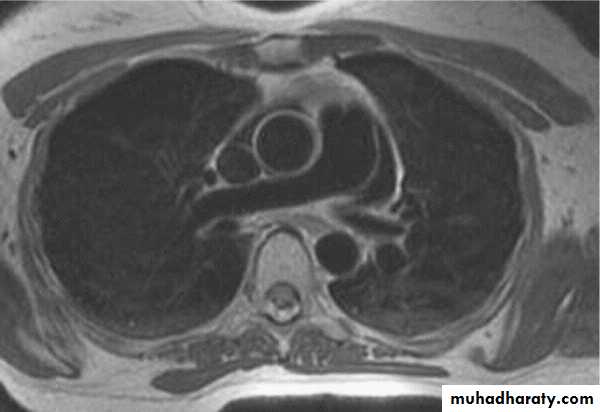

MRI